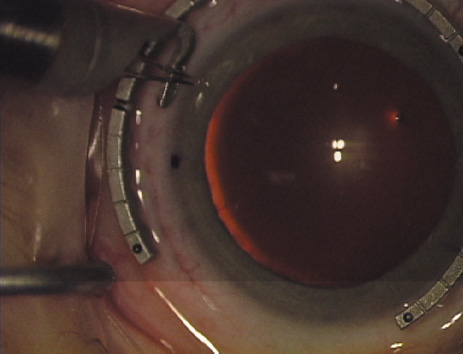

Another less common method of creating peripheral relaxing incisions is

to use a device such as the Terry/Schanzlin Astigmatome (Oasis

Medical), which circumvents the need to make a “free-hand” incision. This

trephine-like device has been designed to create

consistent and symmetric peripheral arcuate corneal relaxing incisions. It

uses a vacuum speculum that mates with various reusable templates

that are selected based upon the amount of astigmatic correction that

is desired. The incision is created by simply rotating a disposable

steel blade unit that fits inside of the template (Fig. 7).  Fig. 7. The Terry/Schanzlin Astigmatome. Fig. 7. The Terry/Schanzlin Astigmatome.

|